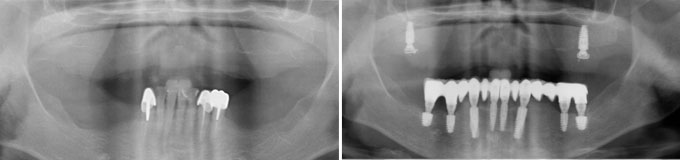

J’ai une maladie des gencives et mes dents tombent les une après les autres, je refuse un appareil que je serais obligé d’enlever

Solution : on va traiter les dents qui sont récupérables et remplacer les autres par des implants.

Implants multiples pour éviter les bridges et redonner des dents individuelles au patient avec traitement d’une maladie parodontale.

Implants multiples pour éviter les bridges et redonner des dents individuelles au patient. État final.